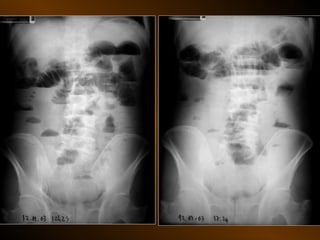

KHÍ TỰ DO

TRONG KHOANG PHÚC MẠC

NGUYÊN NHÂN

thủng tạng rỗng

nguồn gốc xuyên phúc mạc

nguồn gốc trong phúc mạc

10 – 15% thủng tạng rỗng → không thấy hơi tự do ổ bụng

TỤ KHÍ NGOÀI PHÚC MẠC

• Nguyên nhân :

– Thủng tạng rỗng

– Áp xe tạo khí

• X quang quy ước

• Siêu âm

• XQCLĐT